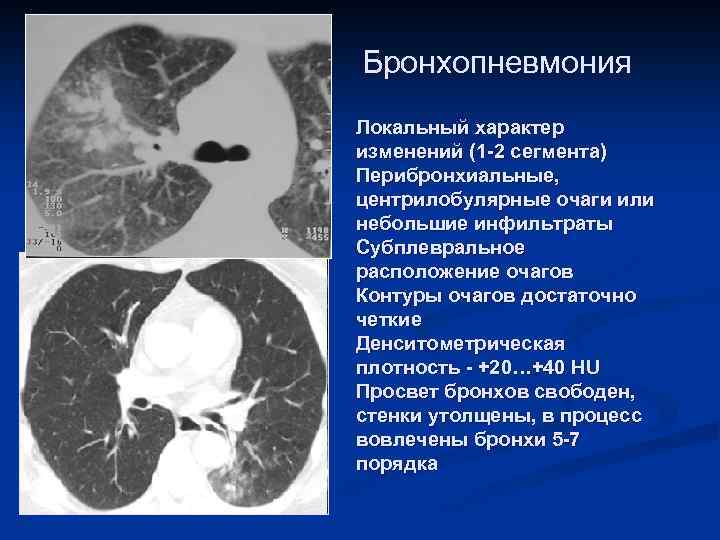

- Центрилобулярные очаги - Симптом «дерева в почках» - Утолщение стенок бронхов

Бронхопневмония Локальный характер изменений (1 -2 сегмента) Перибронхиальные, центрилобулярные очаги или небольшие инфильтраты Субплевральное расположение очагов Контуры очагов достаточно четкие Денситометрическая плотность - +20…+40 HU Просвет бронхов свободен, стенки утолщены, в процесс вовлечены бронхи 5 -7 порядка

Очаги инфильтрации в ндоле сочетаются с усилением легочного рисунка и расширением корня Легочный рисунок усилен, что подчеркивает пестроту картины Корни реактивны Нет четкой границы по ходу междолевой плевры. М. б. очаги в соседних долях